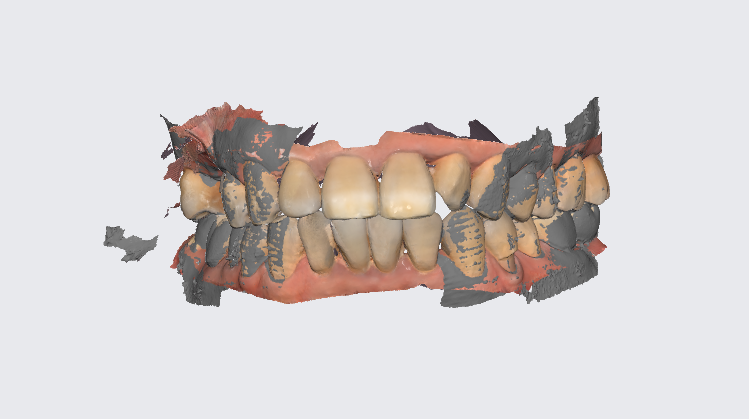

구강스캐너를 사용하여 보철을 제작하였는데요.

전악 치아를 다 촬영하다보니

좌,우 치아 비교도 가능하고

윗니 어금니 관계도 고무인상재보다는 좀 더 정밀하게 채득이 가능하죠~